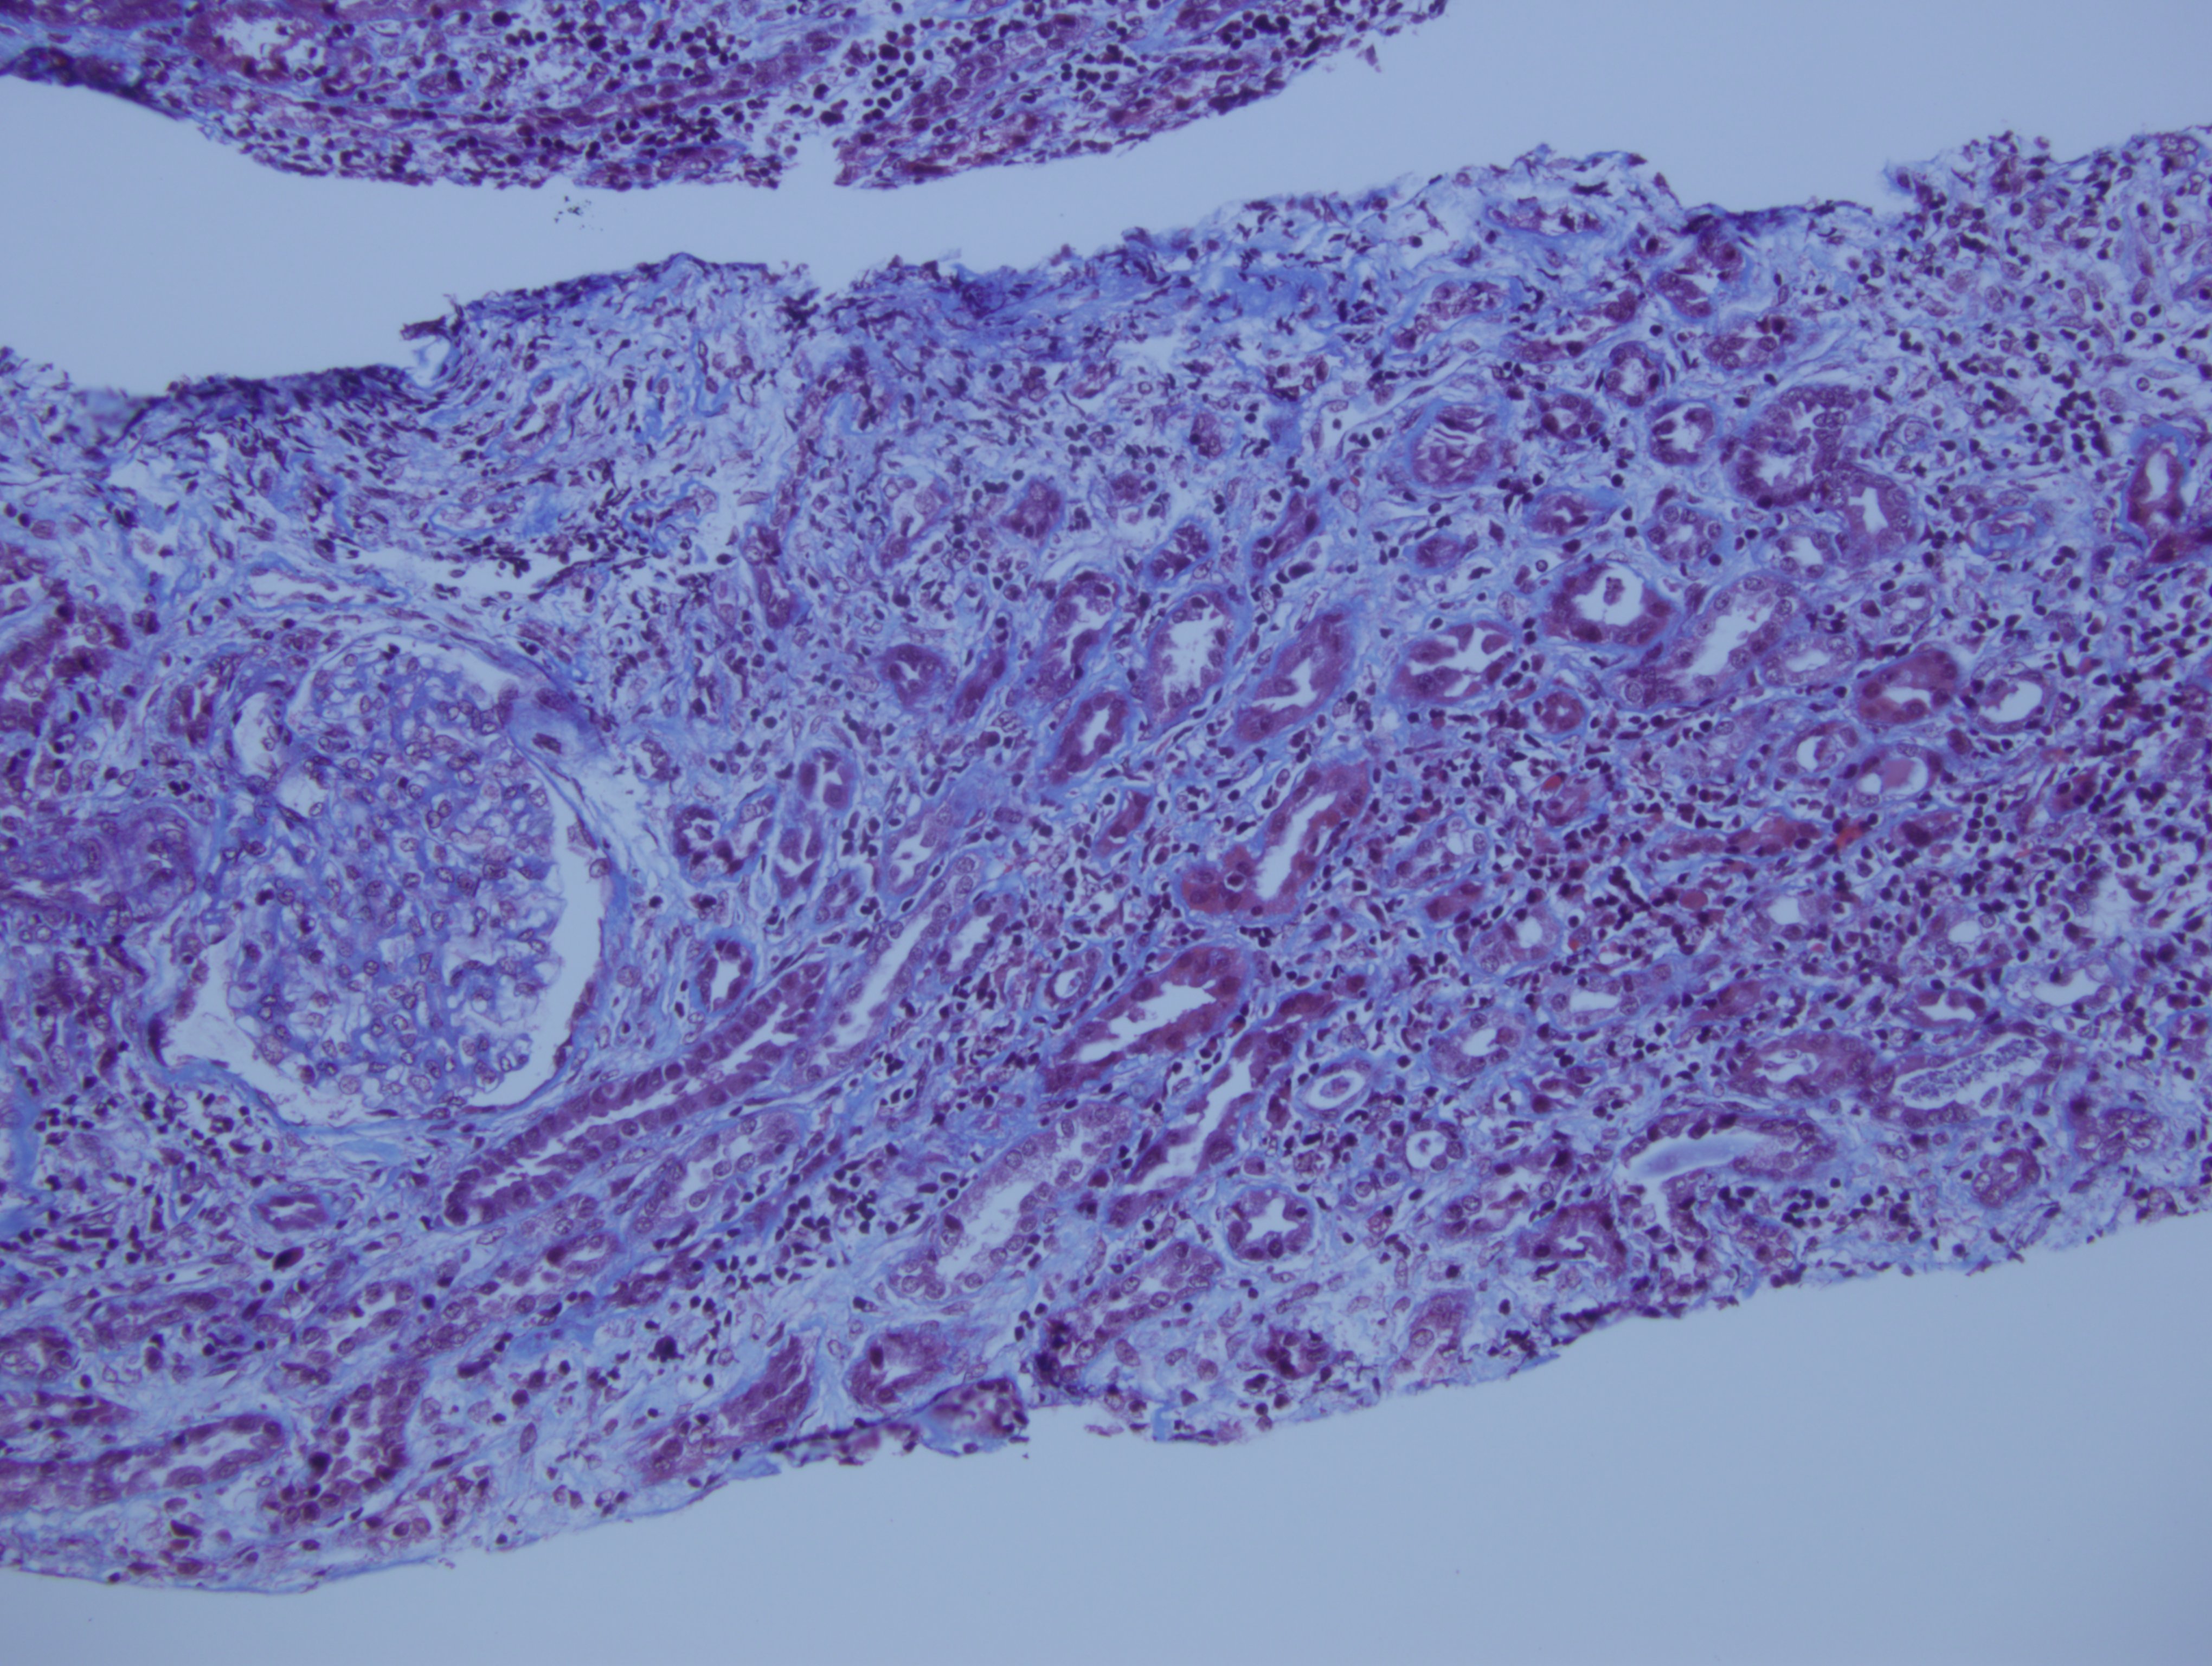

Biopsia renal, tricormico

Nefritis tubulo intersticial por leflunomide